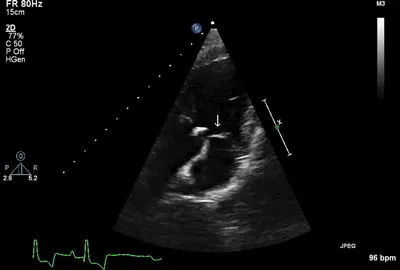

Imaging ResultsThoracic radiographs and abdominal ultrasound were unremarkable. Two-dimensional, M-mode, color flow, and spectral Doppler echocardiography demonstrated a vegetative lesion associated with the aortic valve, moderate aortic regurgitation, mild thickening of the mitral valve, and mild left atrial enlargement (Figures 1 and 2).

Figure 1 (above): Left parasternal long-axis view: A hyperechoic lesion associated with the aortic valve was noted (arrow), consistent with a vegetative endocarditis lesion.